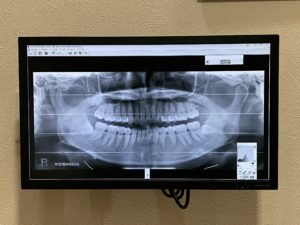

7)レントゲン撮影〜歯と歯茎の検査

1.レントゲン撮影

必要な部分のレントゲンを撮影します。

レントゲンを撮影することで、むし歯の進行度合い、歯周病の進行度合いなどを診断します。また、親知らずの有無や状態なども確認できます。

当院では最新のデジタルレントゲンを設置しており、患者さんのご負担を最小限に抑えることができます。(ピアスなど金属類は画像に乱れが生じるので外しての撮影をお願いいたします。)